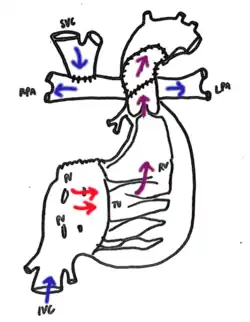

Bidirectional Glenn. Cavopulmonary anastomosis is created connecting the SVC to the right pulmonary artery. Any previous supply to the PAs, such as a Norwood-procedure shunt, is removed. | |

In the bidirectional Glenn shunt procedure, the surgical aim is to control pulmonary blood flow and volume load on the heart. This must be balanced with adequate oxygenation and systemic delivery of oxygenated blood. This modified circulatory system is established by detaching the superior vena cava from the right atrium and connecting the cranial part of the SVC to the pulmonary arteries (shunt). This is an example of a surgical anastomosis. As a result, the venous blood from the upper body enters the SVC and perfuses the pulmonary circulation as a low-pressure circuit, similar to a two-ventricle circulatory system. However, the remainder of systemic venous returns through the inferior vena cava continuing to mix with oxygenated blood returning from the pulmonary circuit.[4]